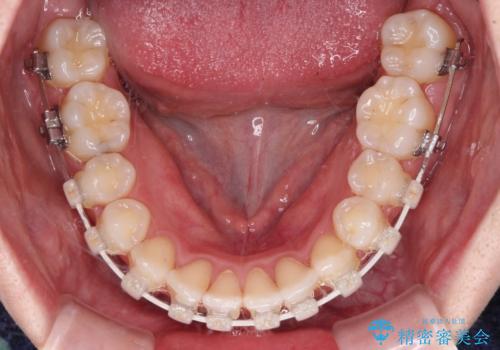

- 矯正装置

- 審美装置

歯列矯正では基本的に骨格を改善することはできませんが、急速拡大装置(MARPE)を使用することで上顎骨を側方に拡大させることができ、咬合状態を大きく改善することができます。

事前に急速拡大装置で側方拡大を行い、上下を目立たないワイヤー装置により歯列を整えていくこととしました。